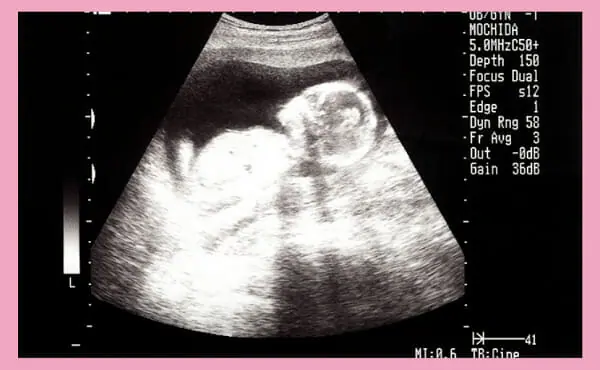

妊娠15週目のエコー写真です。

妊娠15週の時期には赤ちゃんの外性器も形成され、エコー検査では赤ちゃんの身体の向きによって、性別が判断できることも少なくありません。なお、医療機関によってはエコー検査による性別の判断結果を教えてもらえないことがあるため、事前に確認すると良いでしょう。